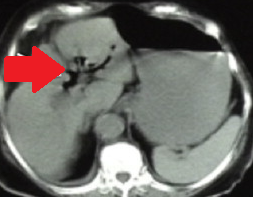

Contrast-enhanced CT of the abdomen, revealing air in intrahepatic biliary tree (pneumobilia) (red arrow)